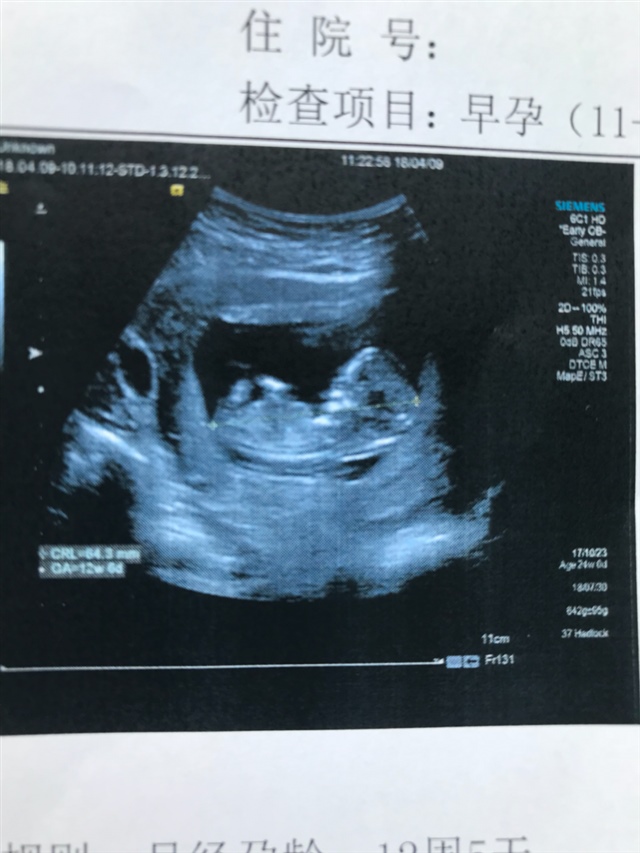

产前检查 B超